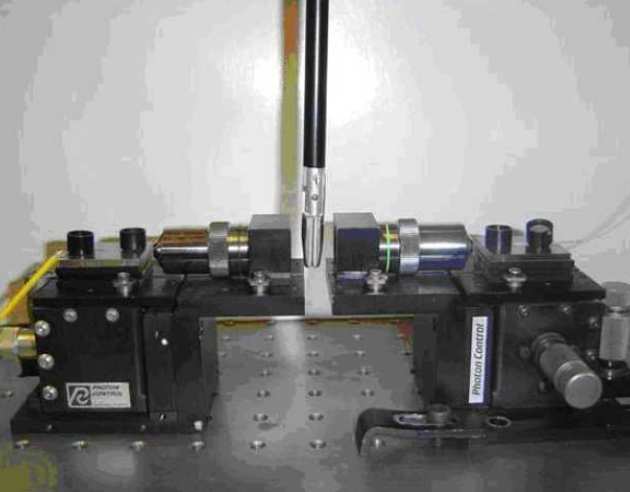

Timmy Floume, Richard Syms, George Hanna, Ara Darzi (St Mary’s Hospital)

|

|---|

| Lab-based optical measurement of RF tissue fusion |

Radio frequency (RF) tissue fusion is a novel method of tissue approximation that can seal tissue without the need for sutures or staples, based on tissue transformations induced by Joule heating and mechanical pressure. RF delivery must be controlled and optimised to obtain a reproducible, reliable seal. At present, tissue impedance is used for feedback during RF blood vessel sealing. We have developed a method of real-time optical measurement to improve understanding of the tissue modifications induced by RF fusion. Near infrared transmission spectroscopy has been used for dynamic acquisition of the tissue attenuation spectrum, and the modified Beer-Lambert law has been used to extract optical parameters. Simultaneous temperature measurement shows that tissue coagulation alters scattering losses and that tissue dehydration induces changes in the water absorption band near 1450 nm wavelength.

|

|---|

| Experimental arrangement |